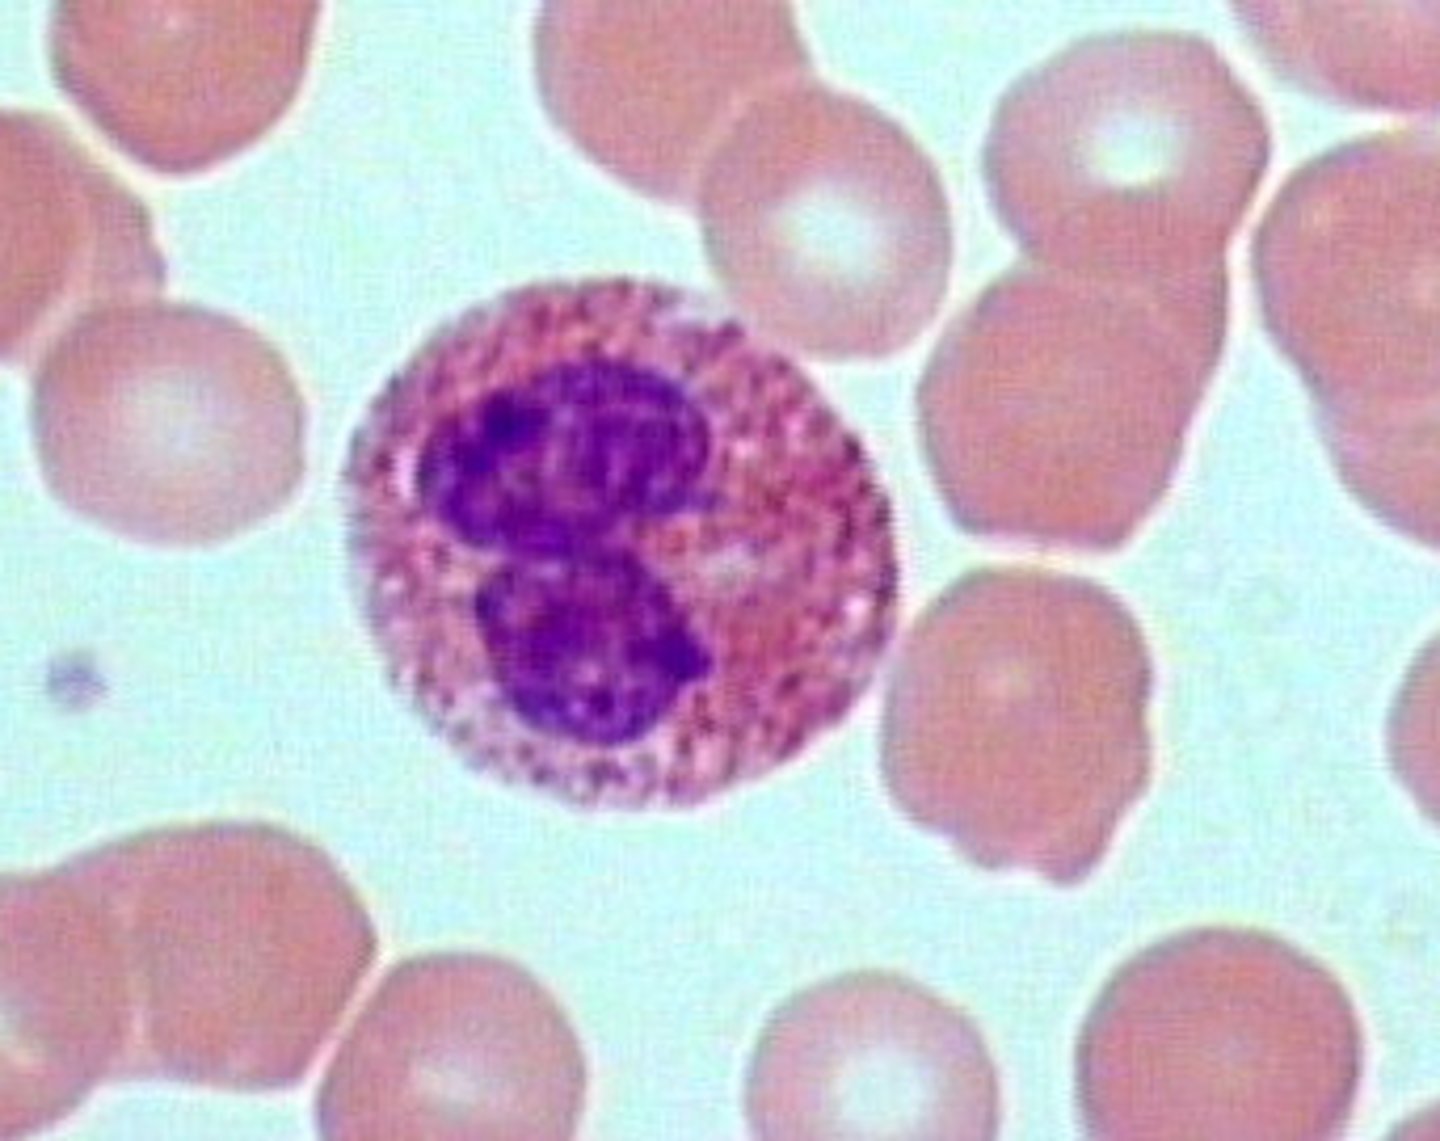

Blood

What is this?

Abnormal

Is this blood slide normal or abnormal?

Eosinophil

what is this?